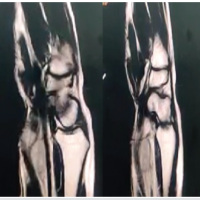

A 36-year-old man, clerk by occupation, came to orthopedic outpatient depart in B.K.L. Walawalkar rural medical college and hospital Dervan in May 2019 with complaints of difficulty in performing right (dominant hand) ringer finger movements for the past 3–4 months. Formation of fist was associated with a clunk in palm and, pain and heaviness in radial side of hand, that is, the thumb, index, middle finger, and ring finger. Opening of fist relieved all the symptoms. He had no history of trauma and no comorbidities. On clinical examination, there was triggering of the right ring finger at palm. No obvious swelling was noted. There was no wasting of thenar eminence. In extension on deep palpation, a firm swelling was palpable in palm along the ring finger which moved proximally along the flexor tendon of ring finger and disappeared on flexing the ring finger. In this position, the patient developed pain and heaviness along the radial three fingers. Tinel’s sign was positive only in this position. Phalen’s test was negative. Transillumination test was negative. In X-ray, no abnormality was noted. Ultrasound showed a well-defined hypoechoic partially compressible focal oval lesion, measuring 19 × mm in size with no vascularity inside, and arising from FDP of the right ring finger, located just distal to palmer aponeurosis. This swelling moved longitudinally along the FDP of ring finger during flexion and extension of ring finger. Median nerve was normal. These findings were suggestive of lipoma/giant cell tumor of FDP tendon of ring finger. After counseling, pre-operative and pre-anesthetic check-up patient was posted for excision of the lump. Regional block was given and tourniquet used. An ulnar palmar approach of AO was chosen for this as it facilitated easy exposure of FDP tendon of ring finger as well as distally same could be used to do carpal tunnel release (Fig. 1, 2, 3, 4).

At 2 years follow-up, the patient was clinically and radiologically assessed (Fig. 6). He was completely asymptomatic and performing all his activities without any discomfort or limitations of wrist or fingers. There was no triggering and USG confirmed no recurrence of fibrolipoma.